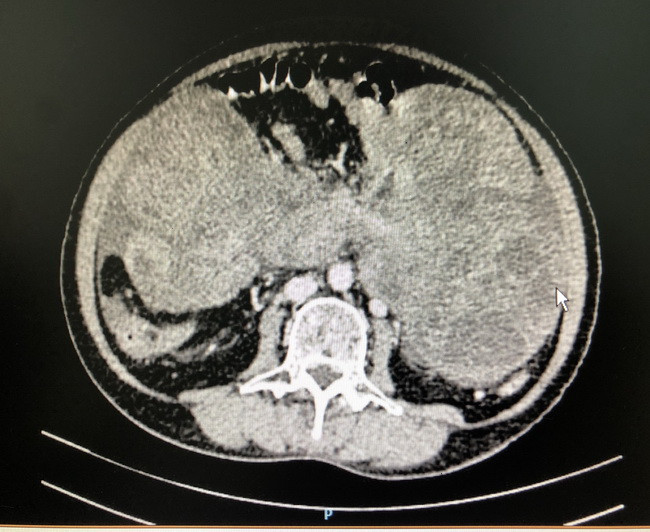

| Hình chụp CT khối u chiếm gần hết ổ bụng bệnh nhân. |

Người bệnh đến khám tại BV Đại học Y dược TP HCM thì được các bác sĩ cho biết khối u đã rất to, chắc và chiếm gần hết ổ bụng.

Bên cạnh đó, kết quả chẩn đoán hình ảnh học cũng cho thấy đây có thể là khối u ác tính và đã có hiện tượng xuất huyết, di căn phúc mạc.

Cô M. được phẫu thuật để lấy khối u ở vị trí mạc treo ruột non có kích thước 23x16x19cm, cân nặng 3kg cùng với phần mạc nối bị di căn.